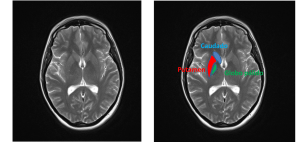

1. Calcificaciones bilaterales localizadas en el estriado (caudado-putamen), globo pálido y núcleo dentado (ver la figura 1. para localización de estas estructuras) visualizado en imágenes de TAC cerebral.

Las calcificaciones cerebrales fisiológicas que aparecen con la edad son pequeñas, de aspecto punteado aunque pueden confluir y limitadas al globo pálido (ver entrada). La calcificaciones que se observan en la calcinosis idiopática estriado-pálido-dentada son más extensas, afectan además del globo pálido al putamen y al nucleo dentado y son confluentes (ver esta imágenes en esta página).